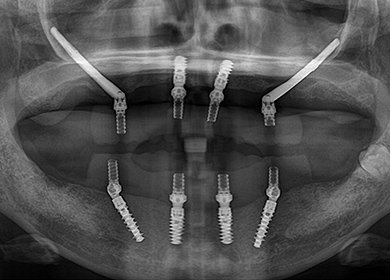

• オールオン4(上顎4本下顎4本)

術前

術後3年以上

年齢・性別 75歳・女性

治療期間 5ヶ月、通院回数18回

治療費用 5,492,080円(税込)

治療内容 1年前に作った入れ歯が痛くなり噛めない。バネも歯肉に刺さると来院。今回は入れ歯ではなくしっかり噛みたいということでオールオン4を希望。